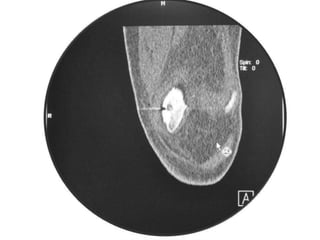

• Excision of the osteoid osteoma nidus using

CT–assisted localization, a Kirschner wire

inserted into the nidus, and a biopsy punch

inserted over the Kirschner wire into the

bone.

• They recommend using a trephine 2 mm

larger than the lesion for complete removal.

• A CT guided needle was passed to localize the

lesion.

CT – Guided Drilling

•

OPD procedure,

Localization of the nidus in CT Scan,

Local anesthesia,

K-wire passed into nidus,

Transferred to OT,

Short GA,

Drilling of the nidus by a cannulated drill,

Complete relief of pain.

Osteoid Osteoma -Tx • Excision of the osteoid osteoma nidus using CT–assisted localization, a Kirschner wire inserted into the nidus, and a biopsy punch inserted over the Kirschner wire into the bone. • They recommend using a trephine 2 mm larger than the lesion for complete removal. • Recurrence after apparently complete excision has been reported but is rare.

• A CTguided needle was passed to localize the lesion. • Through an anterior "Hernia" approach the lesion was approached and excised. • The Follow-up CT Scanning done to reveal complete removal of lesion. • A biopsy confirmed it later.

CT – GuidedDrilling • • • • • • • • OPD procedure, Localization of the nidus in CT Scan, Local anesthesia, K-wire passed into nidus, Transferred to OT, Short GA, Drilling of the nidus by a cannulated drill, Complete relief of pain.